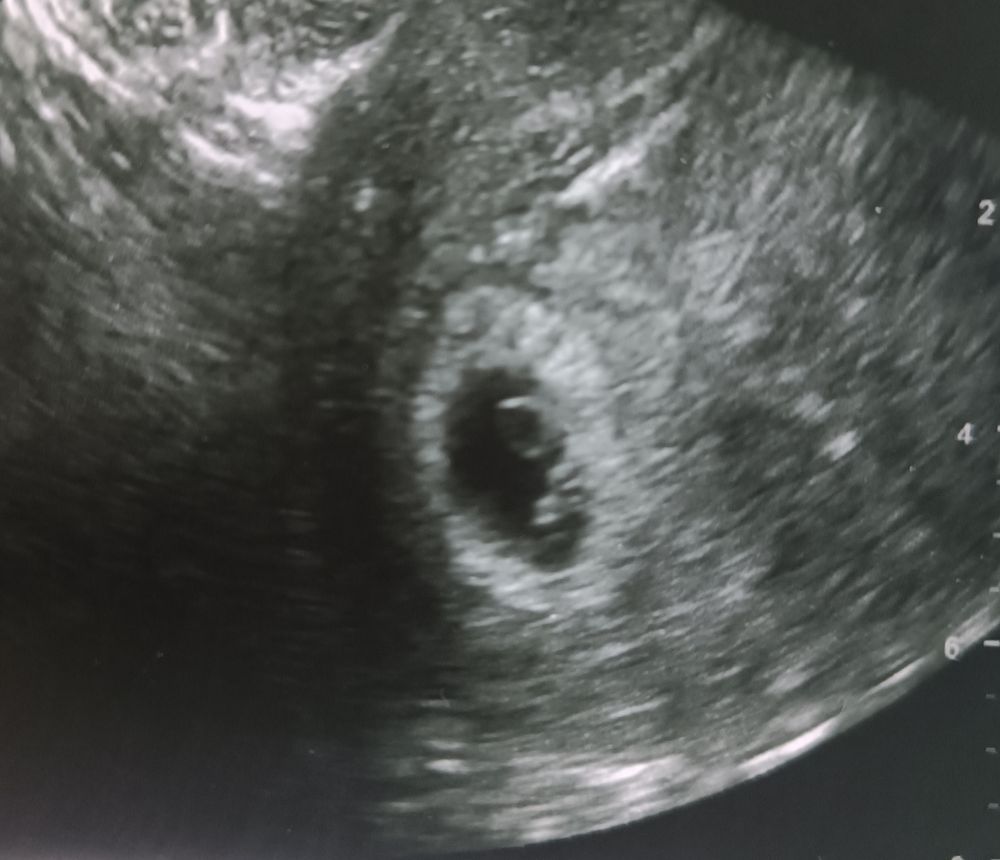

Светик,

Смотрите, сверху вниз. 5 недель, 6 недель, 8 недель. Как тут не увидеть?))